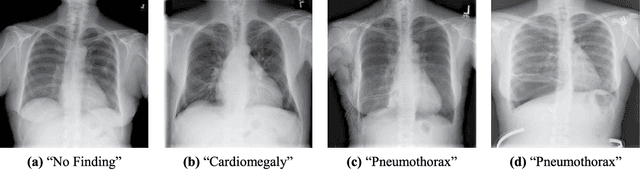

Abstract:The automatic detection of critical findings in chest X-rays (CXR), such as pneumothorax, is important for assisting radiologists in their clinical workflow like triaging time-sensitive cases and screening for incidental findings. While deep learning (DL) models has become a promising predictive technology with near-human accuracy, they commonly suffer from a lack of explainability, which is an important aspect for clinical deployment of DL models in the highly regulated healthcare industry. For example, localizing critical findings in an image is useful for explaining the predictions of DL classification algorithms. While there have been a host of joint classification and localization methods for computer vision, the state-of-the-art DL models require locally annotated training data in the form of pixel level labels or bounding box coordinates. In the medical domain, this requires an expensive amount of manual annotation by medical experts for each critical finding. This requirement becomes a major barrier for training models that can rapidly scale to various findings. In this work, we address these shortcomings with an interpretable DL algorithm based on multi-instance learning that jointly classifies and localizes critical findings in CXR without the need for local annotations. We show competitive classification results on three different critical findings (pneumothorax, pneumonia, and pulmonary edema) from three different CXR datasets.

Abstract:Pneumothorax is a critical condition that requires timely communication and immediate action. In order to prevent significant morbidity or patient death, early detection is crucial. For the task of pneumothorax detection, we study the characteristics of three different deep learning techniques: (i) convolutional neural networks, (ii) multiple-instance learning, and (iii) fully convolutional networks. We perform a five-fold cross-validation on a dataset consisting of 1003 chest X-ray images. ROC analysis yields AUCs of 0.96, 0.93, and 0.92 for the three methods, respectively. We review the classification and localization performance of these approaches as well as an ensemble of the three aforementioned techniques.